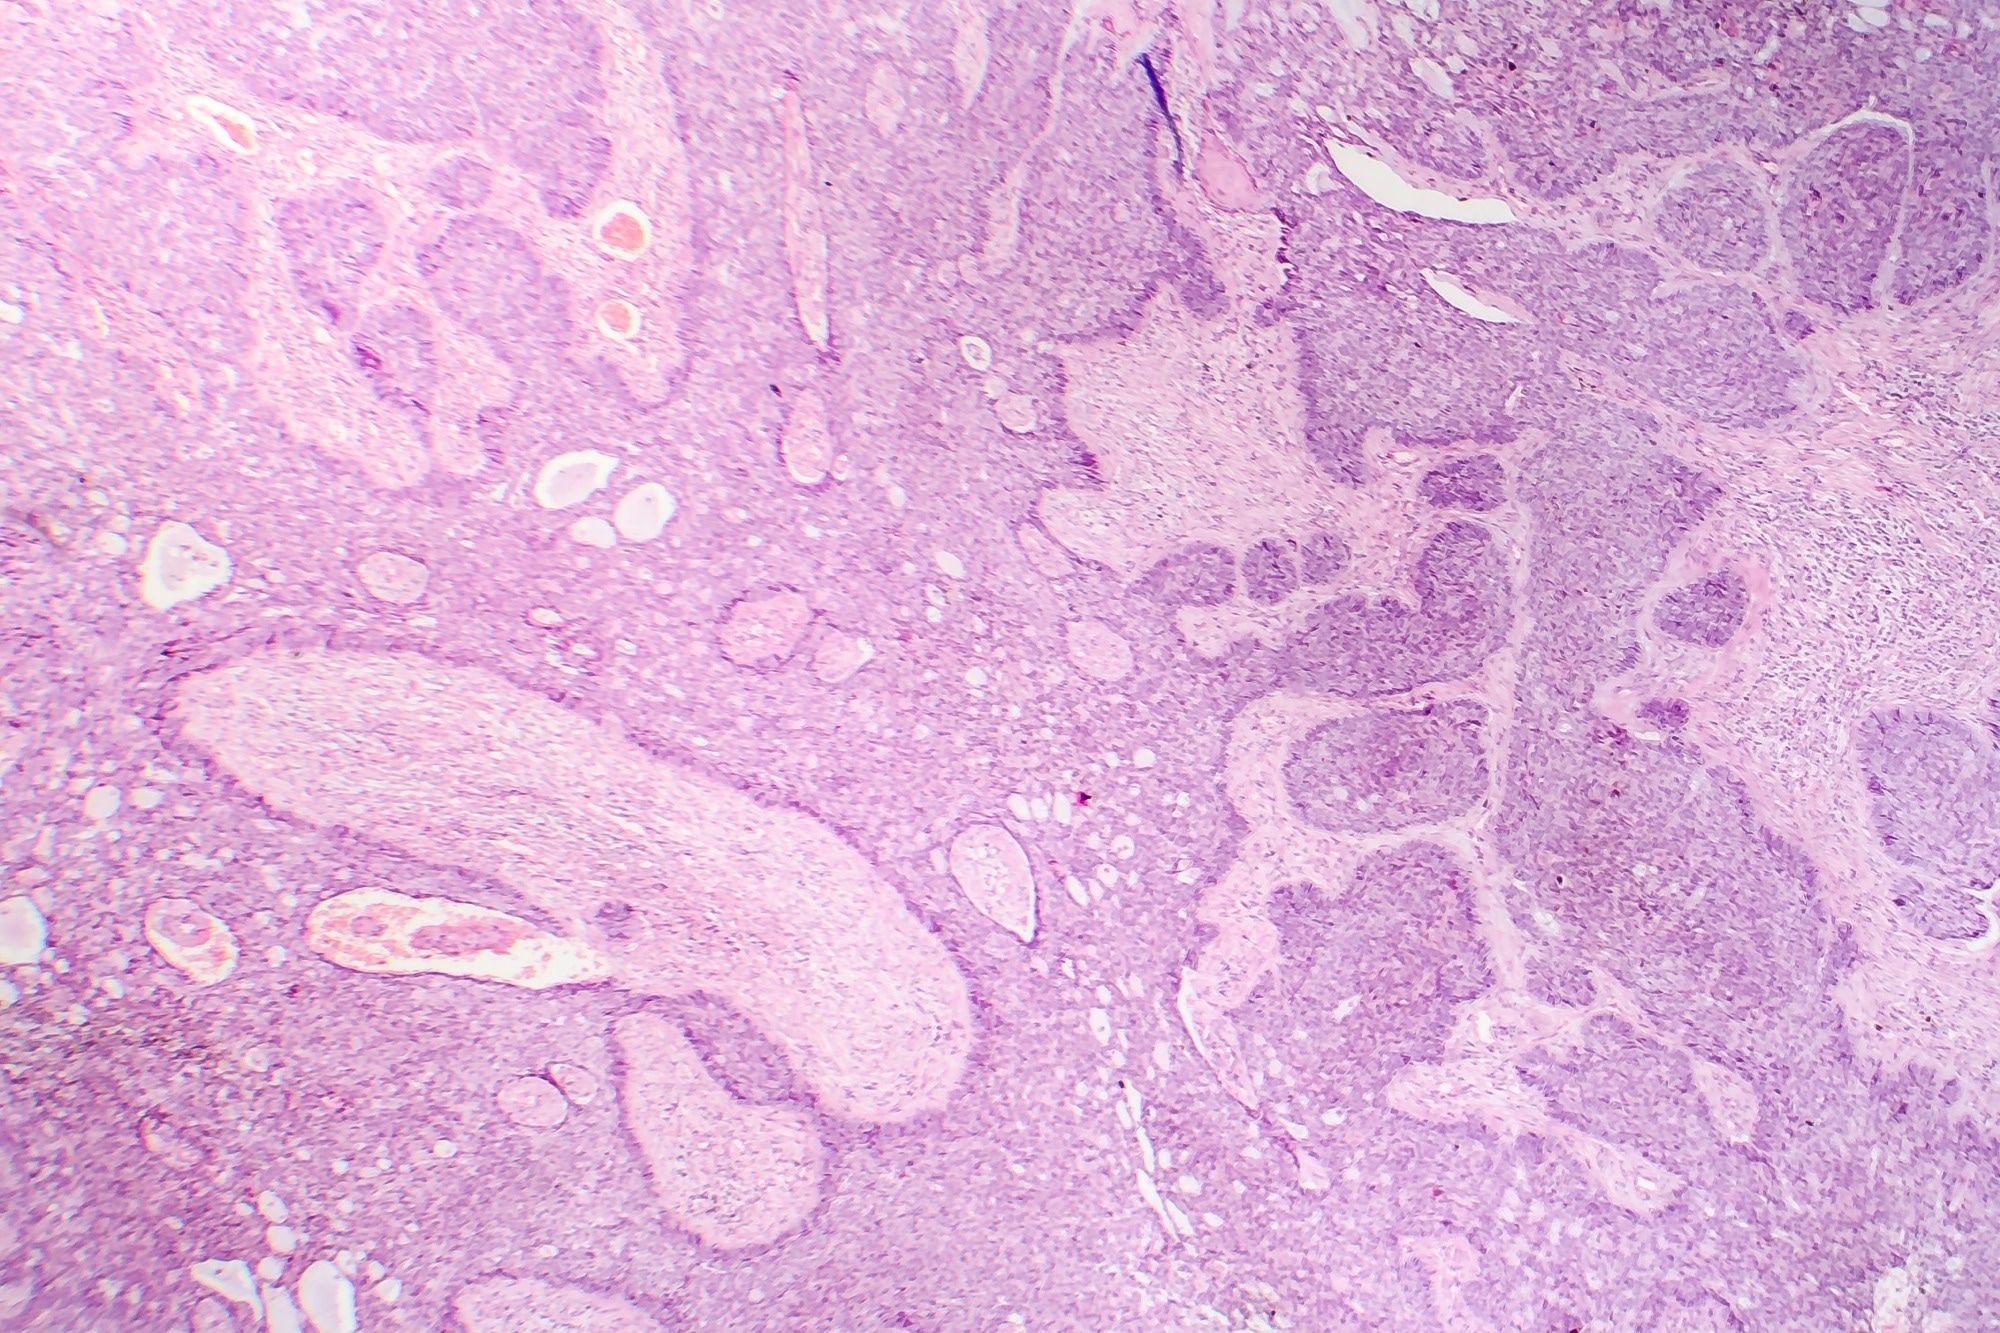

Basal cell carcinoma.Study: Efficacy and tolerability of neoadjuvant therapy with Talimogene laherparepvec in cutaneous basal cell carcinoma: a phase II trial (NeoBCC trial). Image Credit: Kateryna Kon/Shutterstock.com